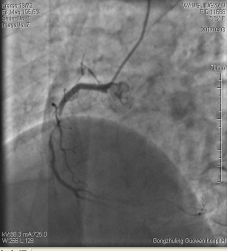

中日聯(lián)誼閆明洲教授向家屬交代病情及介入相關(guān)并發(fā)癥后,患者及家屬同意冠脈支架治療,過(guò)程順利,于右冠脈中段植入Firebird2 2.5*33mm 藥物洗脫支架1枚。

術(shù)前 術(shù)后

患者冠脈支架植入術(shù)后,胸骨后疼痛癥狀明顯好轉(zhuǎn),復(fù)查心電圖抬高的ST段回降。